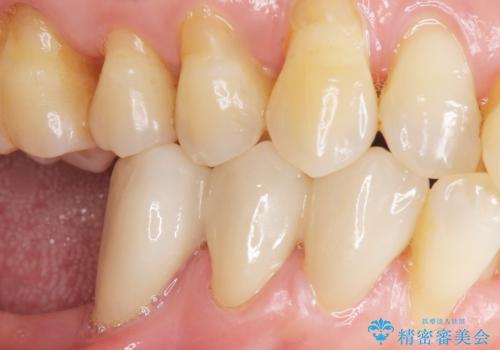

また、咬み合わせが反対になっている上の前歯(左上2)も補綴で形を変えることにより、咬合を改善しました。

気にされていた前歯と奥歯の動揺がなくなったことと自然な仕上がりに喜んで頂けました。

クラウンの種類:オールセラミッククラウン スタンダード